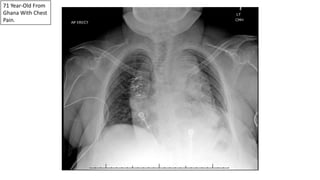

71 Year-Old From

Ghana With Chest

Pain.